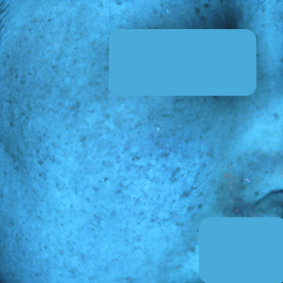

30대 여성 색소 치료 3개월 후기

치료 전 25.08.06 치료 후 25.10.23

현재 피부고민 : 출산 후 짙어진 잡티 및 색소, 피부톤 불균형

치료 전 진단

- 출산 이후 광대, 볼, 이마 중심으로 불균일한 색소 침착과 미세한 멜라닌 축적이 관찰되었습니다.

- 색소는 표피와 진피에 걸쳐 분포해 있었으며, 자외선 노출 시 색소가 쉽게 진해지는 경향이 있었습니다.

- 전체적으로 피부톤이 칙칙하고 투명도가 떨어진 상태로, 색소 완화와 동시에 톤 균일화 및 재발 방지가 필요한 케이스였습니다.

치료 후 변화

- UV 촬영상: 색소 밀도가 전반적으로 감소하며, 멜라닌 분포가 고르게 정리되었습니다.

- NL(일반광) 촬영: 눈에 띄던 잡티와 색소가 옅어지고, 피부톤이 밝고 균일해진 모습이 확인되었습니다.

- 육안상으로도 투명감과 맑은 윤기가 회복되었으며, 시술 후 자극이나 홍반 없이 안정적인 회복을 보였습니다.